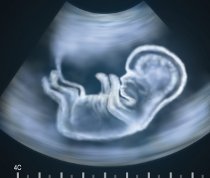

Ranije, ili uobičajeno određivanje pola ploda, obavlja se ultrazvučnim pregledom spoljašnjih genitalija u drugom trimestru trudnoće. U određivanju ambiguous genitalija („neodređene“ spoljašnje genitalije, koje ne odgovaraju ni muškom, a ni ženskom polu), ili razlike između spoljnih genitalija i pola ustanovljenog na osnovu određivanja hromozoma, neophodna je i

Ranije, ili uobičajeno određivanje pola ploda, obavlja se ultrazvučnim pregledom spoljašnjih genitalija u drugom trimestru trudnoće

Razvojem sondi visoke rezolucije, kao što su linearne sonde i/ili vaginalne sonde - moguće je odrediti pol u 12. nedelji, a čak u 98,5 do 100 odsto slučajeva do kraja 13. nedelje trudnoće.

U slučaju tačnog merenja ugla polnog organa u odnosu na osovinski skelet, takođe se dolazi do jako velikog procenta tačnog određivanja pola ploda, pa on iznosi 91,5 odsto u 12. nedelji, 99 odsto u 12. nedelji i četiri do šest dana, a 100 odsto u 13. nedelji i do šest dana.

Za lekare sa manjim iskustvom i slabijom ultrazvučnom tehnikom, bolje je da se određivanje pola obavi u drugom trimestru trudnoće nego u prvom, a zasniva se na izgledu penisa i skrotuma kod muškog pola, i dve ili četiri paralelne linije koje odgovaraju labijama (velikim stidnim usnama) kod ženskog pola.